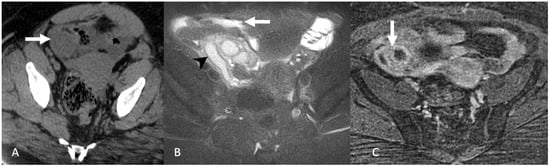

5.2.2. Leiomyoma

5.3. Peritoneal Disease